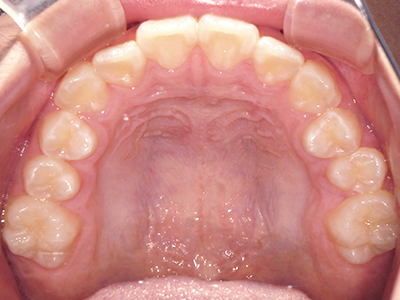

↓ - 上あごが狭くなる

ないき歯科クリニックでは、上あごの成長不足を補い、鼻呼吸を獲得しつつ歯列を整え、将来のお口をより健康な状態にすることをゴールに定める矯正治療をおこなっています。

矯正装置を装着し、調整しながら少しずつ歯を移動させ、歯並びを整えていきます。